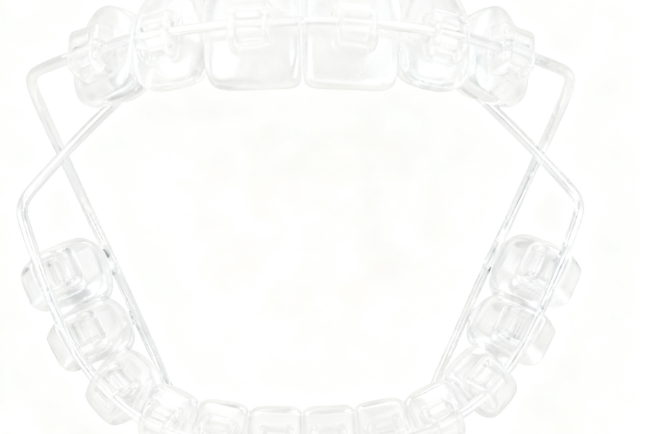

四、SGTB矫正器的佩戴方法指南

1. 正确戴入方法:

首先,可以先从前牙或较难戴入的牙位开始。这是因为前牙比较容易操作,从这里开始可以为后续戴入其他牙齿位置的矫正器做好铺垫。如果后牙错位明显,那么可从错位明显侧先行戴入。然后,双手将矫治器平放入口腔,与牙齿对齐后慢慢戴入。这样可以确保矫正器恰当地贴合牙齿,更好地发挥矫正作用。

2. 摘除技巧:

对于上颌矫正器,扣住后牙腭侧边缘向下轻拉,两侧交替进行。对于下颌矫正器,拇指推起后牙颊侧边缘,两侧交替进行。如果遇到附件,要先轻掀起附件下方边缘再摘下,避免损坏矫正器和附件。